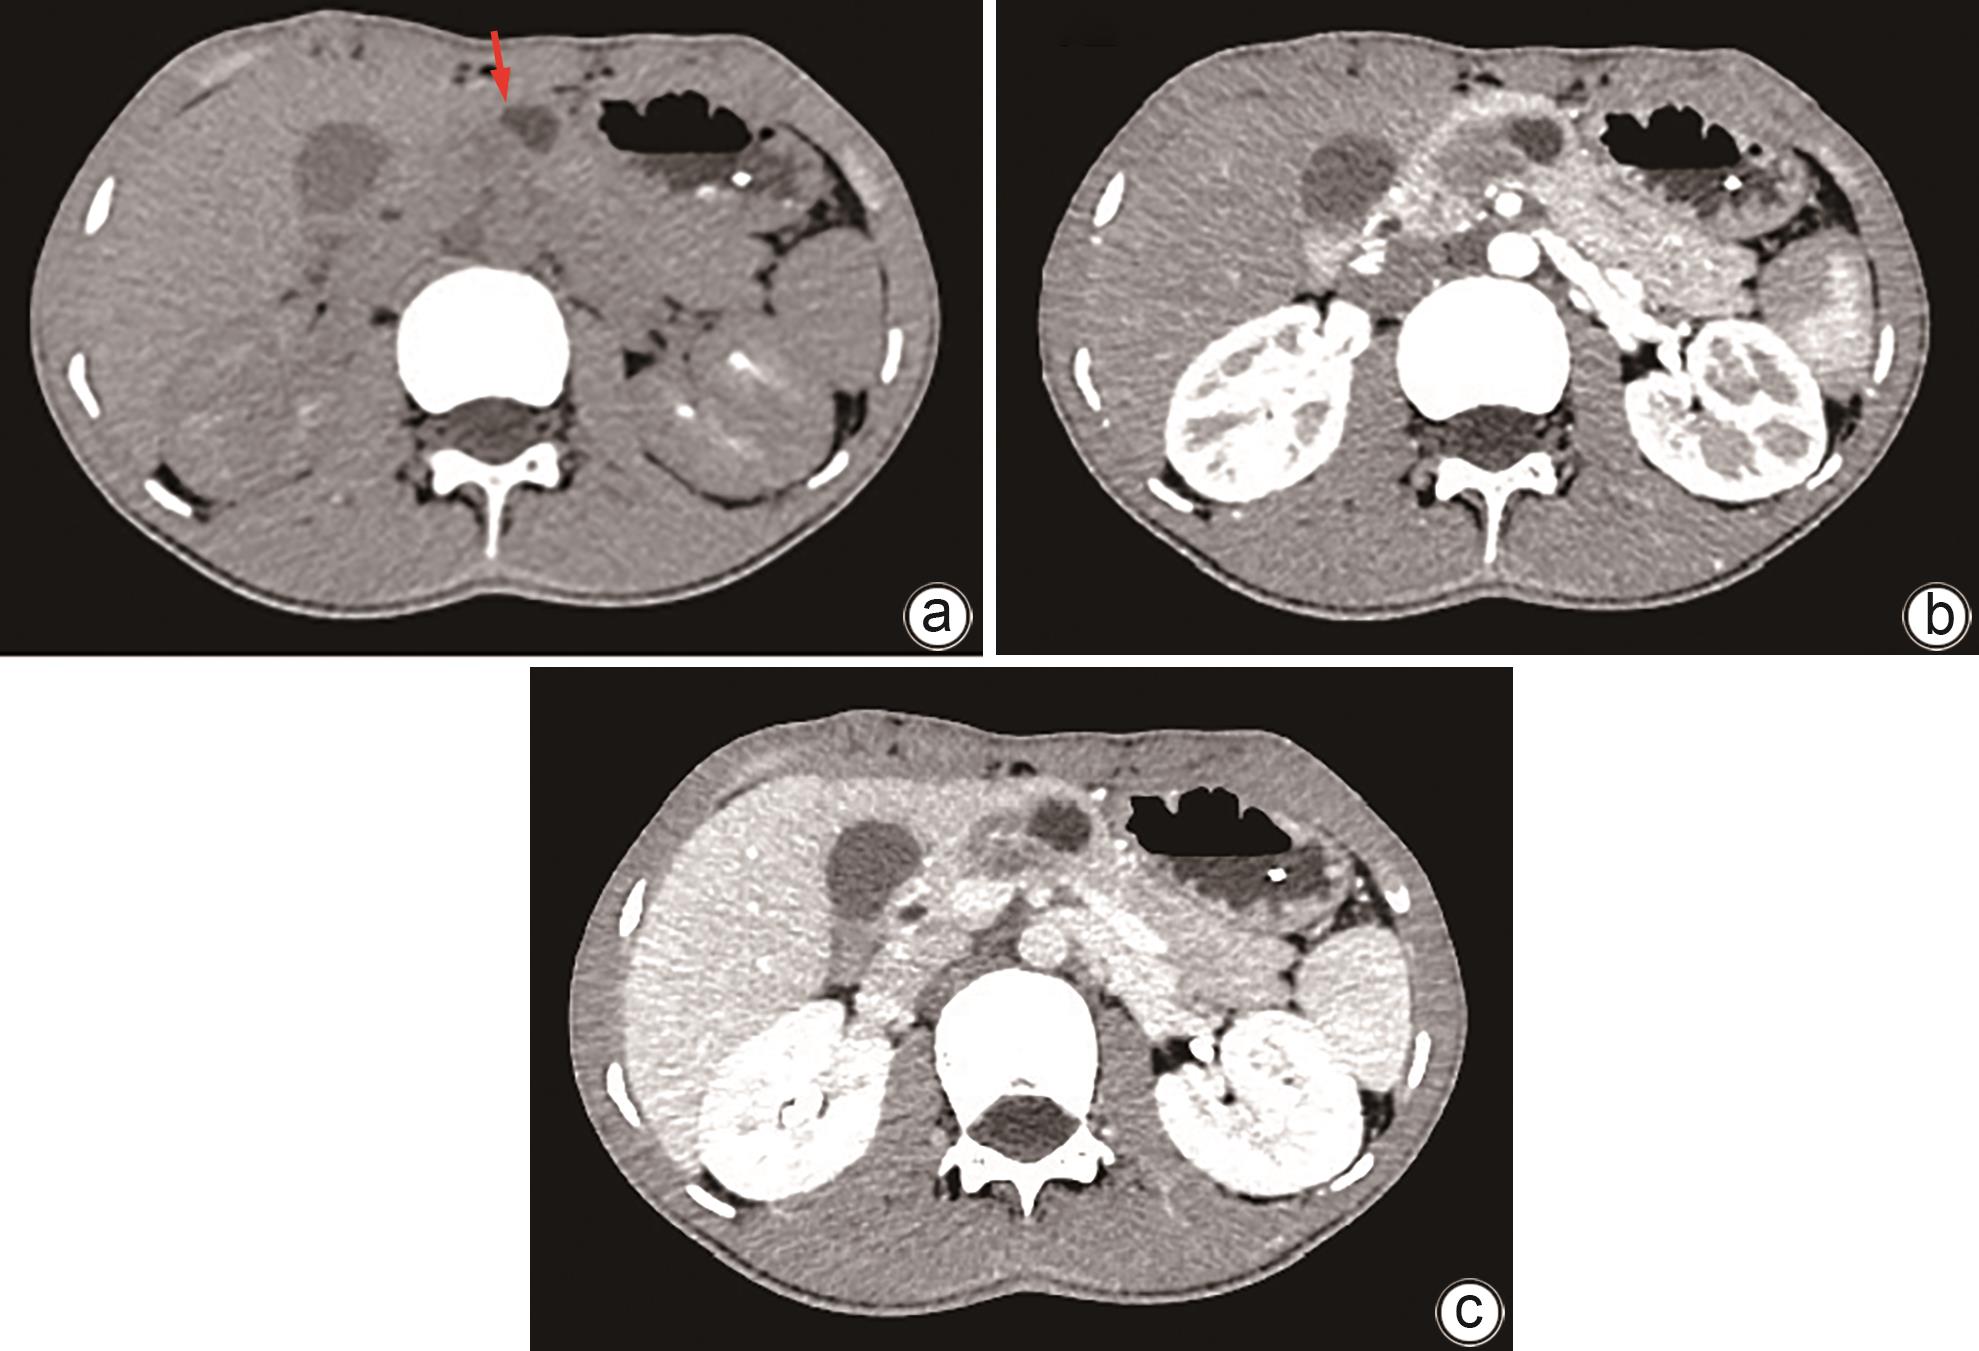

致命性医源性胆道出血的影像学特征和治疗对策

王晨, 王敏, 张科, 张金星, 刘莉, 范志宁

2024, 40(10): 2070-2074. DOI: 10.12449/JCH241022

摘要(987) HTML (349) PDF (2026KB)(76)

摘要:

目的  分析致命性医源性胆道出血(LIH)的影像学特征和发病机制,评价经动脉腔内治疗LIH的价值。  方法  收集2009年8月—2023年7月南京医科大学第一附属医院收治的上消化道出血住院患者269例,对其中确诊为LIH并得到治疗的24例患者的临床资料进行回顾性分析,包括LIH的医源性原因、血管造影结果和动脉腔内治疗方法。23例患者使用明胶海绵颗粒和弹簧圈进行动脉栓塞(TAE),1例患者使用覆膜支架进行隔离。评估疗效的主要标准是手术技术成功率、相关并发症和长期疗效的临床随访。  结果  12例LIH是由介入手术引起,12例是由肝胆胰外科手术所致。主要表现为显著的血压或持续血红蛋白下降(n=13)和上消化道出血(n=18)。2例患者在手术期间即出现症状,4例患者在24 h内出现症状,18例患者在24 h后出现症状。血管造影术显示出血阳性率为100%(24/24)。表现为假性动脉瘤(n=15)、肝动脉截断(n=3)、造影剂外渗(n=5)、肝动脉胆道瘘(n=3)。23例患者行TAE,1例患者行支架置入术。23例患者成功止血,技术成功率为95.8%(23/24)。4例TAE术后出现肝坏死和脓肿。治疗止血后无再出血复发。  结论  多种肝内外医源性损伤均可引起致命性胆道出血且临床及影像学表现多样。综合影像诊断联合动脉腔内治疗是LIH最佳的有效救命措施。